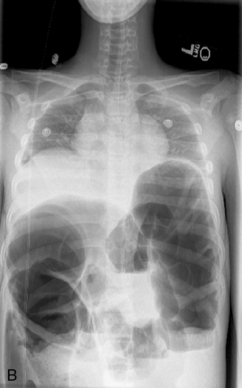

64 Yazigi N.A., Balistreri W.F. Acute and chronic viral hepatitis. In Suchy F.J., Sokol R.J., Balistreri W.F., editors: Liver disease in children, ed 2, Philadelphia: Lippincott Williams and Wilkins, 2001.